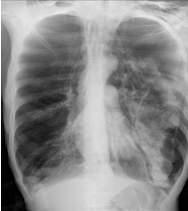

âȘ Table 5: We visualize samples of the generated reports for three cases. We bold the identical descriptions, underline the additional identified findings, and in red the failure findings..

| X-ray Image | Baseline | M2TR | R2Gen | Ours |

|---|---|---|---|---|

![]() |

Pneumothorax gauche de moyenne abondance./Silhouette cardiaque dâaspect normal./Absence dâanomalie mĂ©diastinale./Absence dâĂ©panchement pleural./Absence dâanomalie du gril costal./ | Pneumothorax gauche de grande abondance./Contours cardiaques rĂ©guliers./MĂ©diastin sans anomalies dĂ©celables./ Aucun Ă©panchement pleural dĂ©tectĂ©./Structure du gril costal normale. | Pneumothorax de petite abondance./Aucune anomalie visible au niveau du mĂ©diastin./Pas de prĂ©sence d'Ă©panchement pleural./ | Pneumothorax bilatĂ©ral de moyenne abondance./Configuration normale de la silhouette cardiaque./MĂ©diastin clair, sans irrĂ©gularitĂ©s./Absence d'Ă©panchement pleural./Aucune lĂ©sion du gril costal observĂ©e./ |